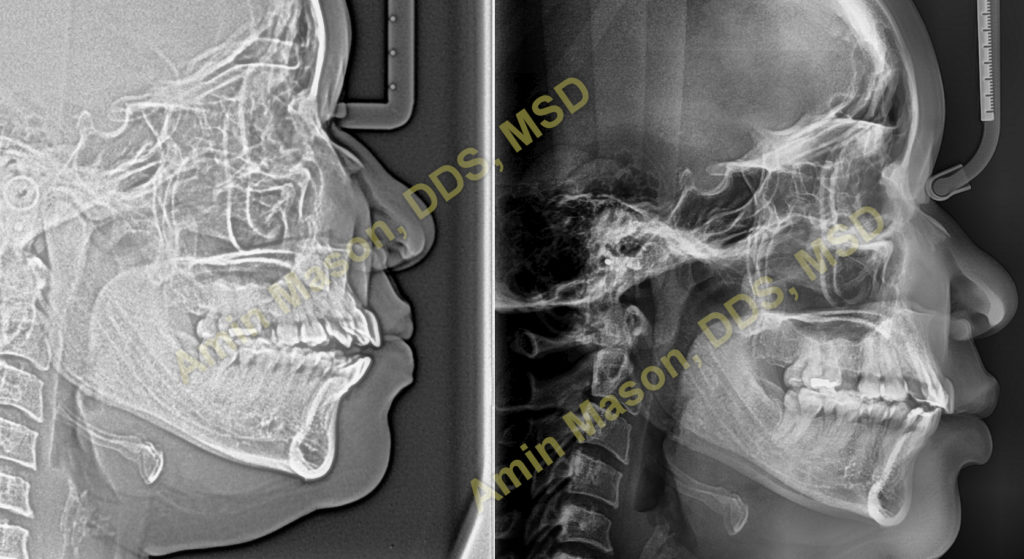

This patient visited our office to correct a severe openbite. The patient presented with low tongue posture and front teeth protruding forward. Per our diagnosis, we treated her with Invisalign Clear Aligners and temporary anchorage devices (mini-implants). With use of TADs, the open bite was corrected without surgery. Patient achieved great results after 20 months and is waiting to receive several dental implants to restore missing teeth.